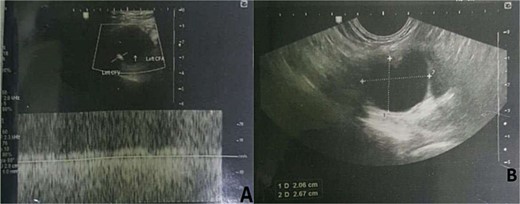

Up on surgical side evaluation, there was a 3 × 2 cm inguinal, slightly tender, firm mass with associated ipsilateral swollen leg. There was a leg-leg discrepancy of 5 cm and 2 cm at the calf and mid-thigh, respectively. His Doppler ultrasound showed left inguinal cystic mass (2.5 cm × 2.4 cm) in the femoral sheath compressing the CFV, but without communication. The blood flow in the compressed CFV was sluggish with no evidence of DVT (Fig. 1). CT venography also showed similar results (Fig. 2). He was then admitted to the surgical ward with the radiologist’s and operating surgeons’ impression of adventitial cystic disease (ACD) of the CFV, and he was scheduled for surgical excision of the presumed ACD.

Doppler ultrasound showing left inguinal cystic mass in the femoral sheath compressing the CFV, with no evidence of DVT.